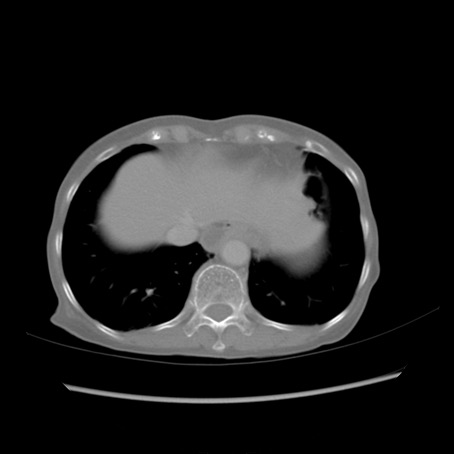

症例25(横断像)

【症例】80歳代女性

【主訴】胸のつかえ感

【現病歴】約9時間前に食後から胸のつかえた感じあり、嘔吐あり、来院。

【既往歴】胃癌(全摘)、胆摘、虫垂炎

【身体所見】心窩部に圧痛あり、反跳痛なし。

【データ】WBC 5700、CRP 0.05